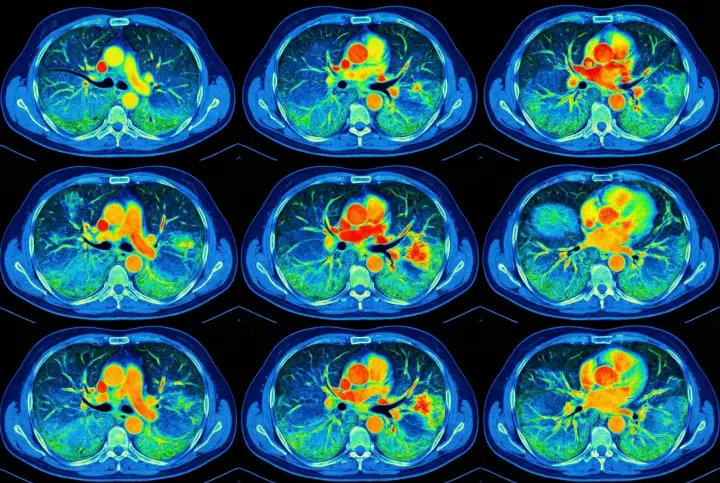

2. COPD progression - the silent suffocator

Untreated lung congestion and airway inflammation often develop into full-scale COPD.

It may begin with mild shortness of breath or an occasional cough-but the damage continues silently.

Before patients realize what's happening, their lung capacity has already declined significantly.